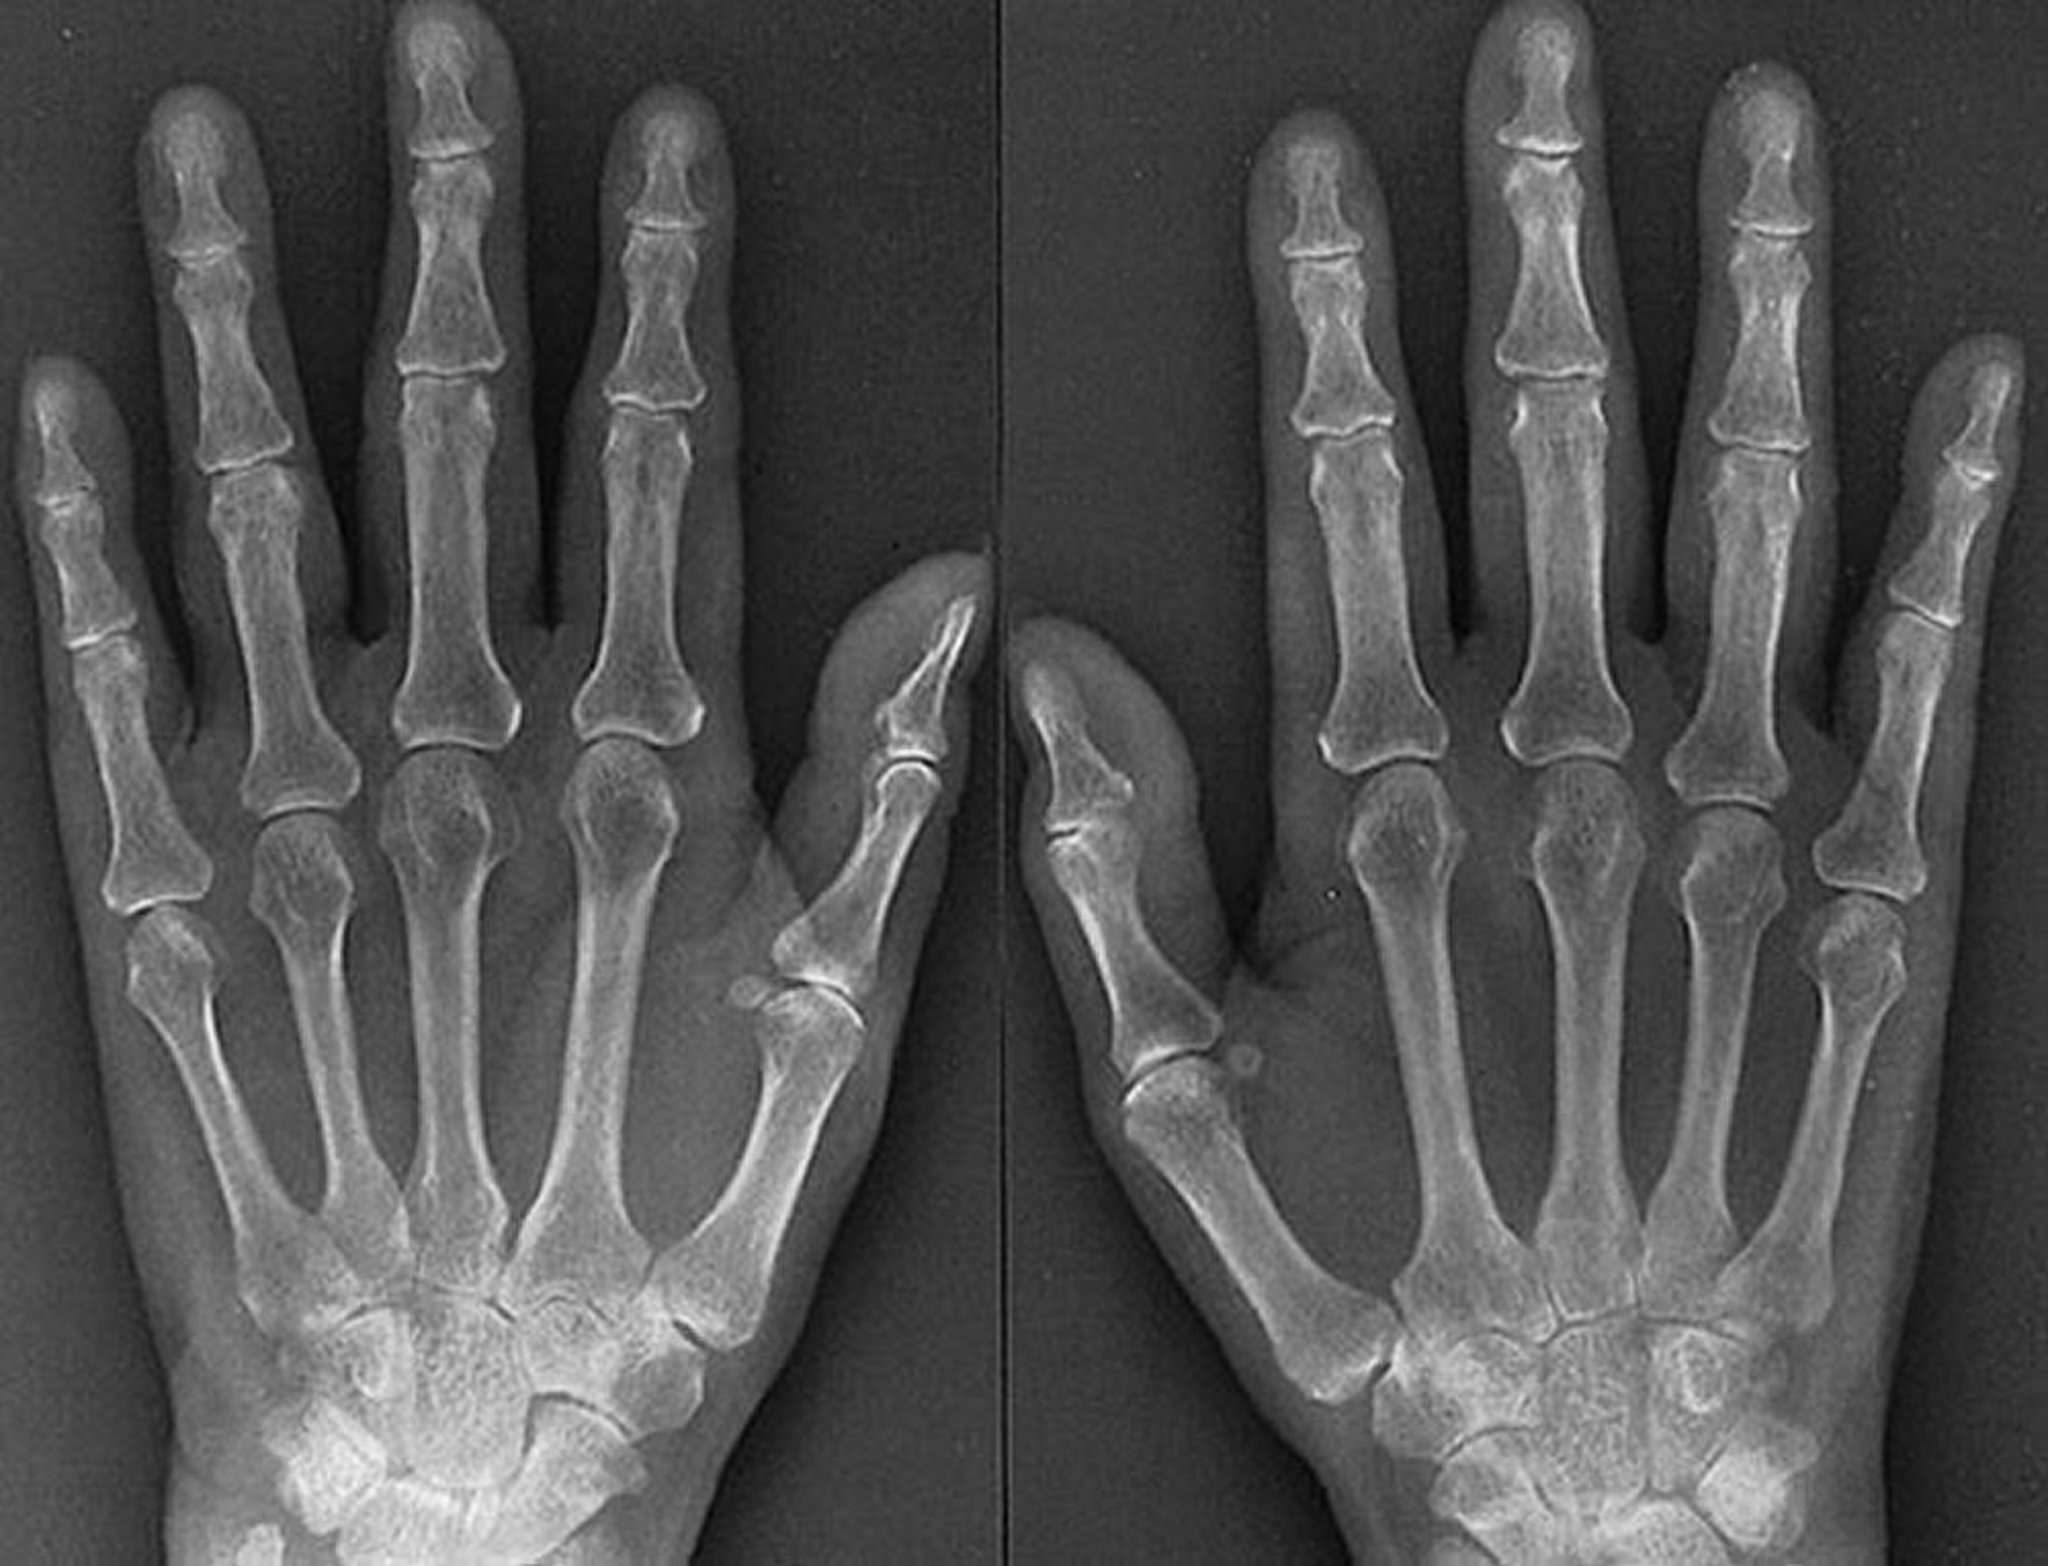

Рентгенологічні особливості ранньої стадії ревматоїдного артриту

Features of aggressive, early rheumatoid arthritis, as seen in this radiograph of a 61-year-old woman with rheumatoid arthritis for 1 year, include evidence of soft-tissue swelling of the metacarpophalangeal and proximal interphalangeal joints, periarticular osteoporosis, symmetric joint space narrowing of several metacarpophalangeal and proximal interphalangeal joints of both hands, and subtle erosions of the right 3rd and right and left 4th metacarpophalangeal joints.

By permission of the publisher. From Matteson E, Mason T: Atlas of Rheumatology. Edited by G Hunder. Philadelphia, Current Medicine, 2005.